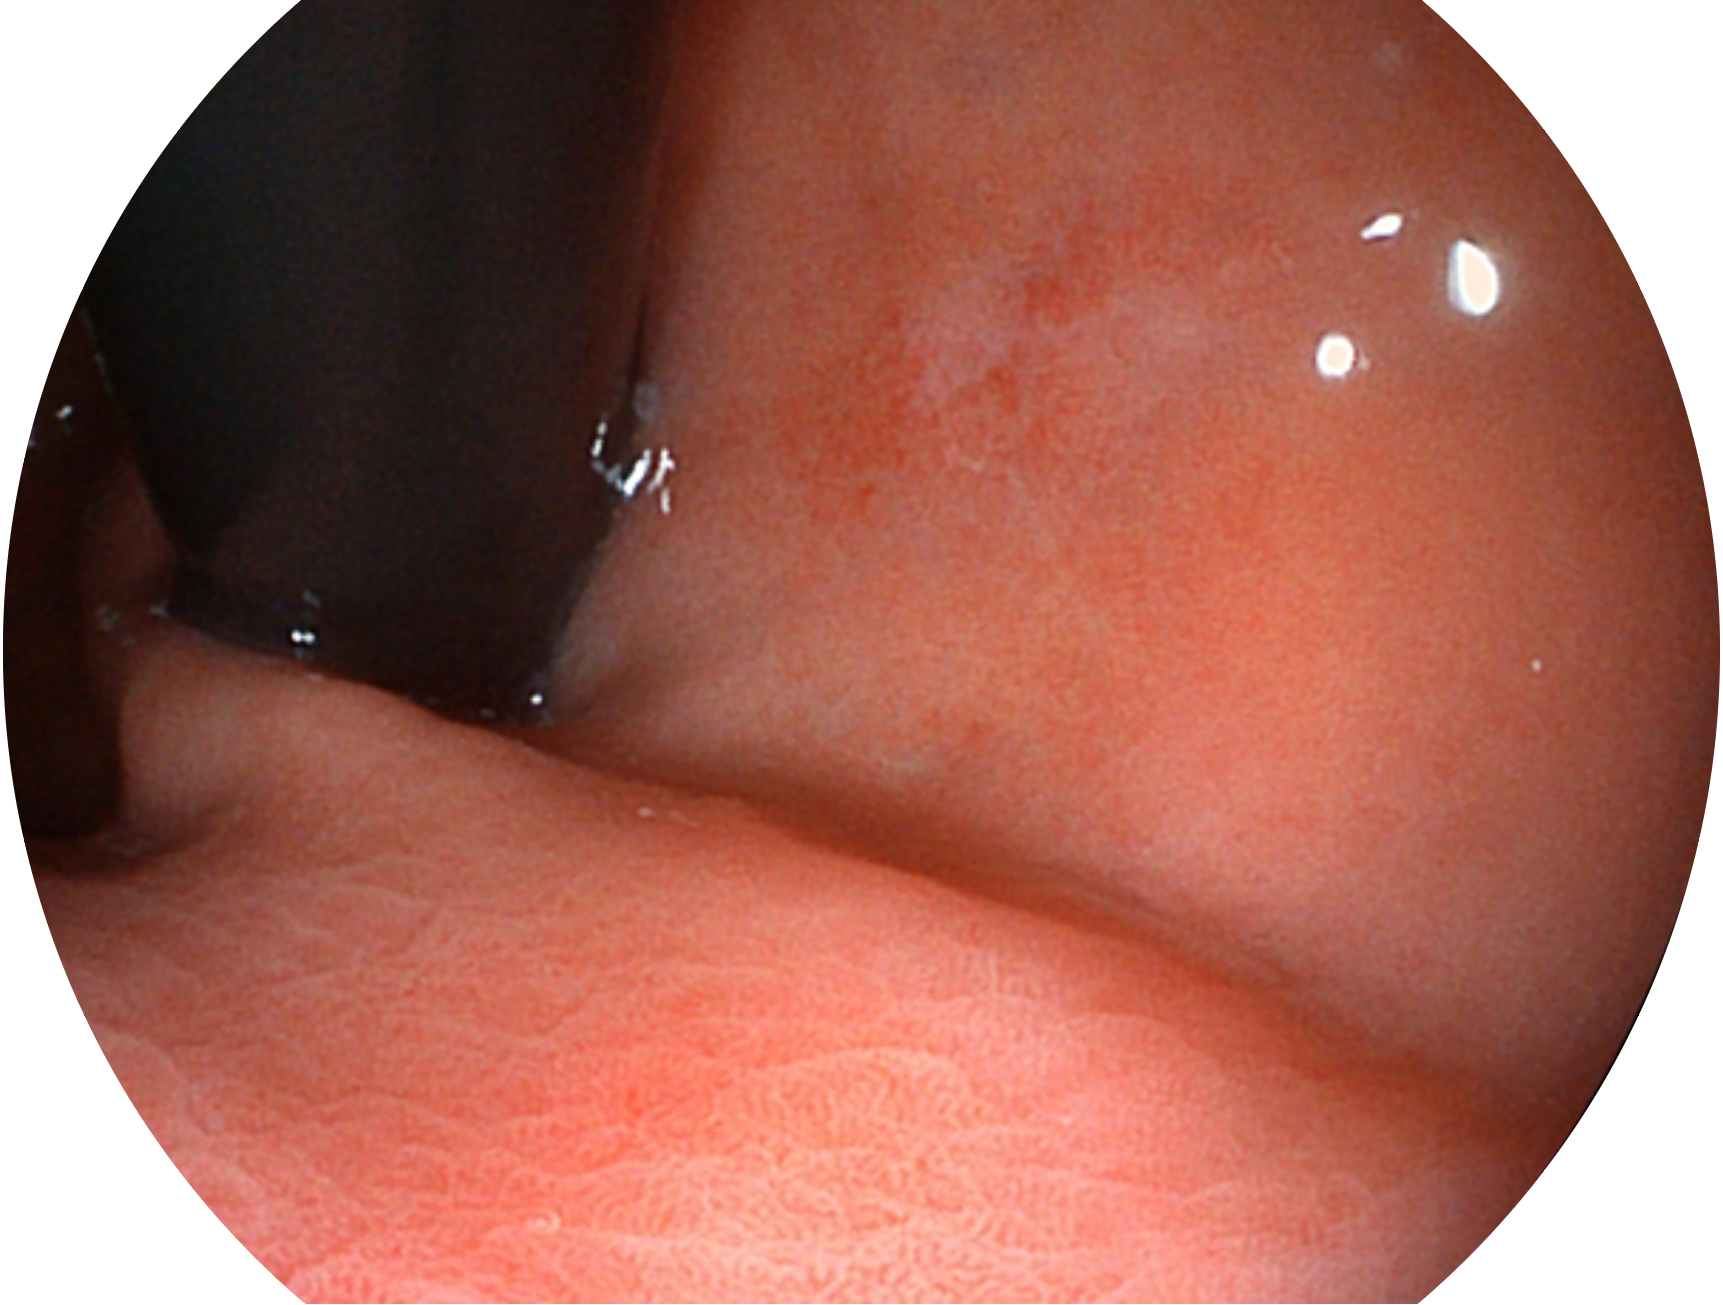

狗万官方网站新开发的内镜染色技术,主要是基于多波长LED 光源的开发,VLS-55Q 四波长LED 光源是由四个不同颜色的LED光按照相应照明模式所规定的特定发光比例进行合束后形成,合束后形成的照明光的光谱由红光、绿光、蓝光及蓝紫光这四个不同的波段范围构成。具有更高光谱自由度,通过光谱比例的控制,实现了聚谱成像技术,英文全称为“Spectral Focused Imaging, SFI”,缩写为“SFI”和光电复合染色成像技术,英文全称为“Versatile Intelligent Staining Technology, VIST”,缩写为“VIST”。